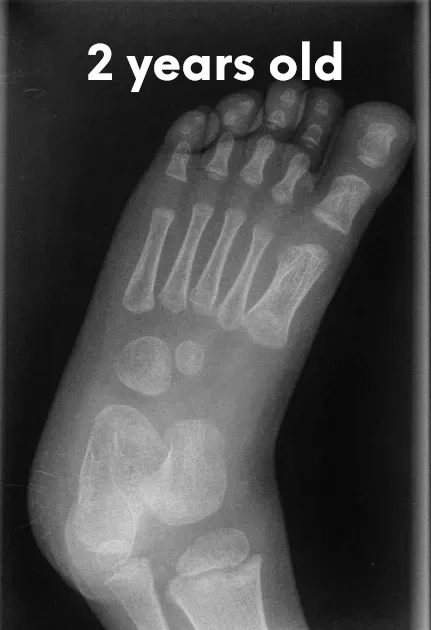

The pictures below will let you understand how babies' feet are developed. Here you can see how bones develop:

2 Years Old

18 YearsDear parents, children’s feet are developing structures, and the absence of an arch is a typical stage of development. Detailed X-RAY pictures above let us understand that babies' foot bones are not connected till the teen years. Only at the age of 14 may we consider that the bones in the feet have reached their connections. At the age of 18, we have fully completed foot structure, where muscles and bones create the whole support system.

Flat feet are a normal stage of development for children under the age of 3. The arch on the inside of the foot has not yet formed, and as children grow and walk, the soft tissues in the feet gradually tighten, shaping the arch over time. Most children have what is called a flexible flatfoot, where the arch only appears when they sit or tiptoe.